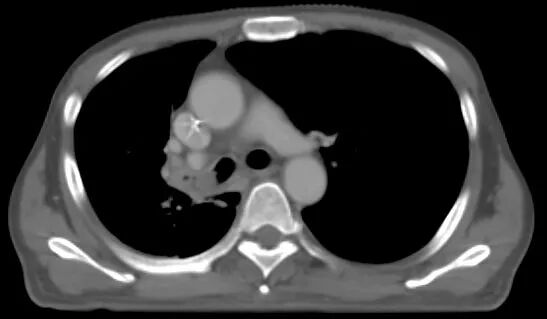

当地医院的检查结果让他大吃一惊:肺癌。气管镜结果并不乐观,肺部的病灶已经完全阻塞了右侧支气管。ewb帝国网站管理系统

(病灶完全阻塞右侧支气管)ewb帝国网站管理系统